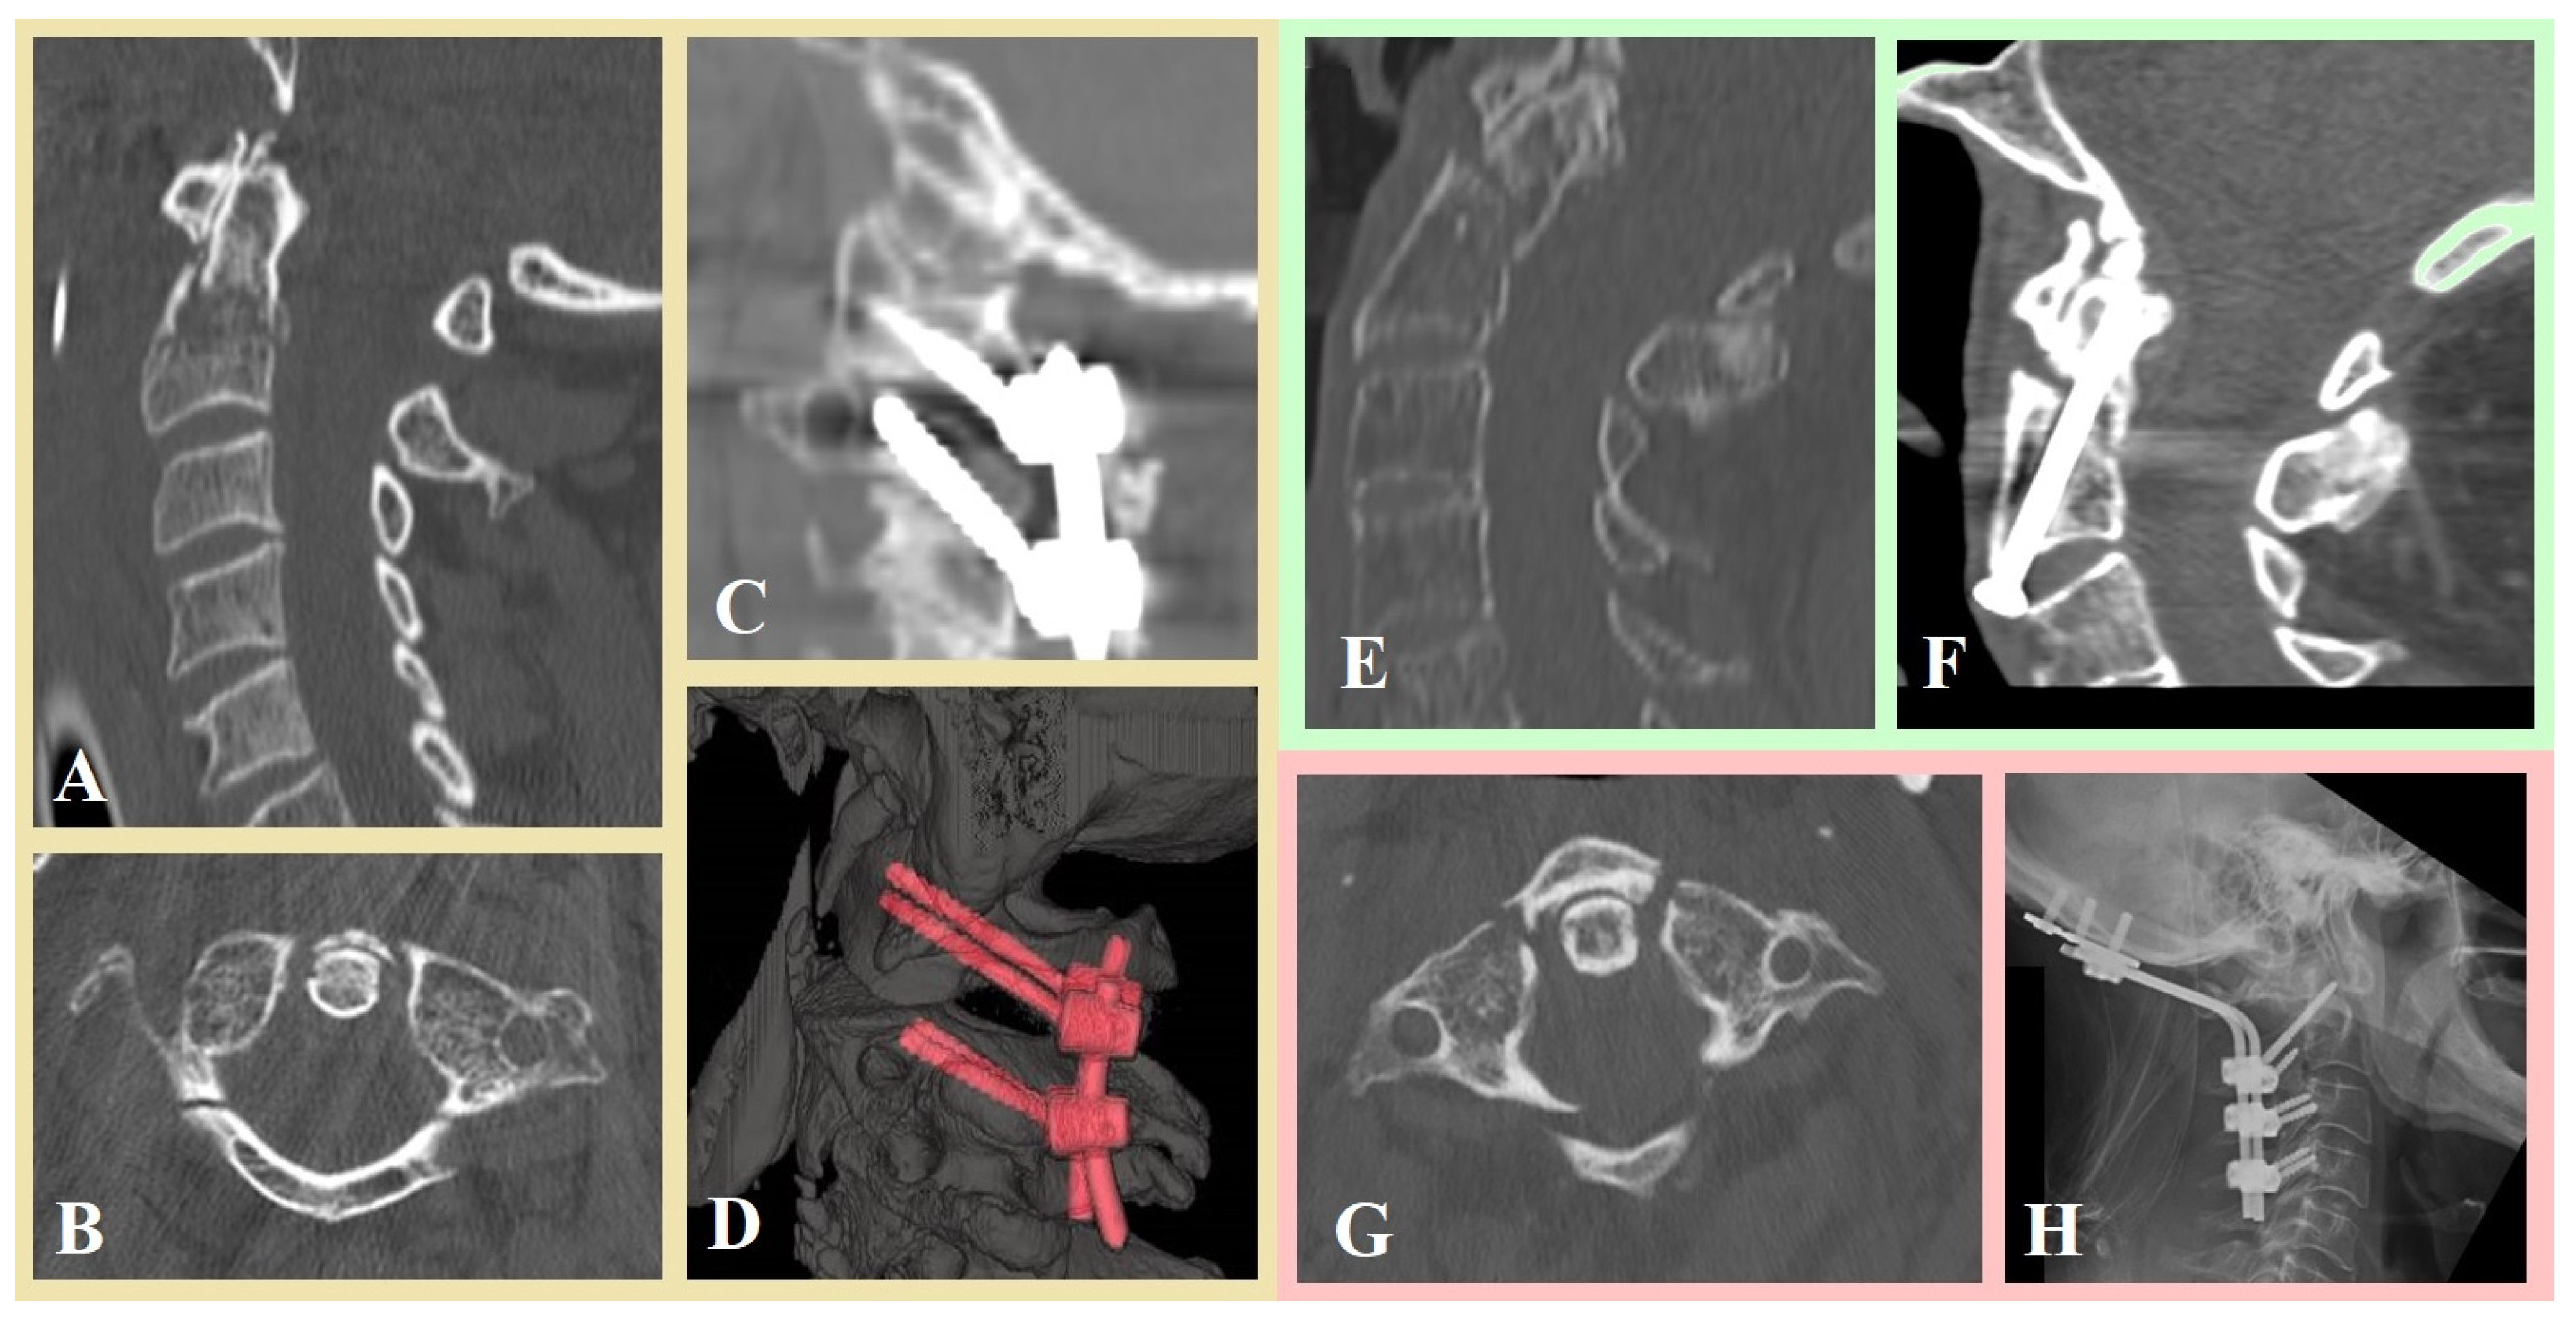

- Montemurro, N.; Carnesecchi, S. Is Direct Transpedicular C2 Fixation (Judet Approach) a Timeless Technique to Learn for C2 Fractures? Glob. Spine J. 2025, 11, 21925682251367412. [Google Scholar] [CrossRef]